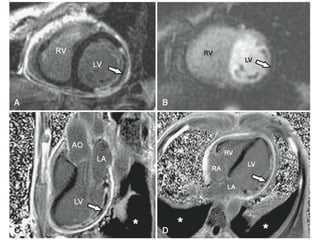

• #49 a transmural MI involving the lateral LV wall associated with a large and dense area of microvascular obstruction (arrow). B, Despite successful epicardial revascular- ization of the infarct-related coronary artery, first-pass myocardial perfusion imaging demonstrates a dense perfusion defect indicative of no-reflow (arrow) matching in location with the infarct. C, D, Long-axis LGE images confirm the extensive area of microvascular obstruction involving a large extent of the lateral LV wall. Of note, there was concurrent intense pericardial inflammation and bilateral pleural effusion

• #81 47 year-old man with no prior medical history presented with dizziness and a junctional rhythm with frequent premature ventricular contractions on a resting electrocardiogram. CMR revealed mildly reduced LV systolic function with akinesis of the basal and midinferior and inferolateral walls. LGE images (A, long axis; B, short axis) demonstrate midmyocardial and epicardial LGE (arrows). In A, apart from the inferolateral midwall enhance- ment (bottom arrows), there was a second focus of LGE seen in the basal septum (top arrow). This pattern of midmyocardial and epicardial LGE is consistent with an infiltrative process, such as sarcoidosis. AO = aorta; LA = left atrium; RV = right ventricle.